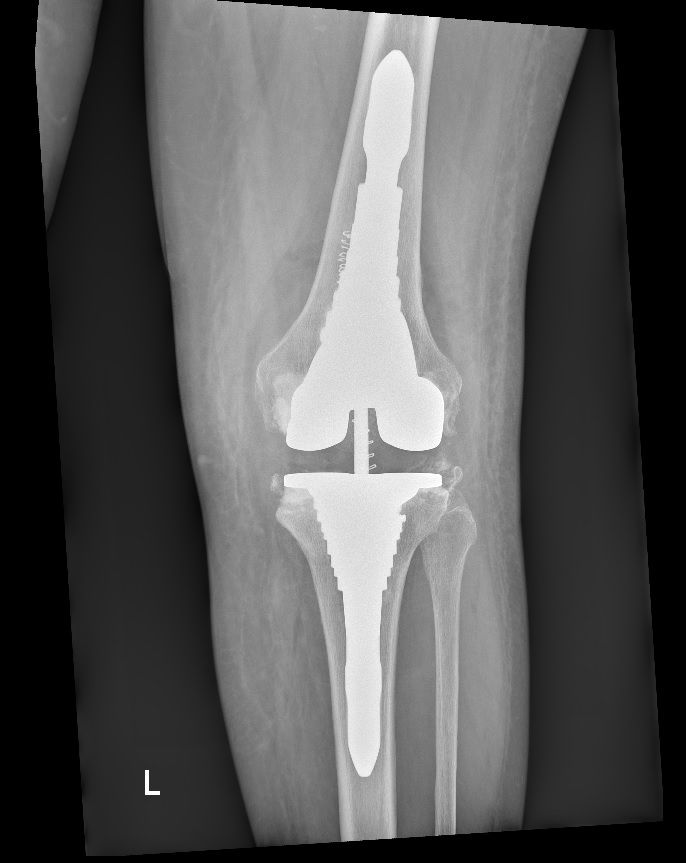

Foto e video